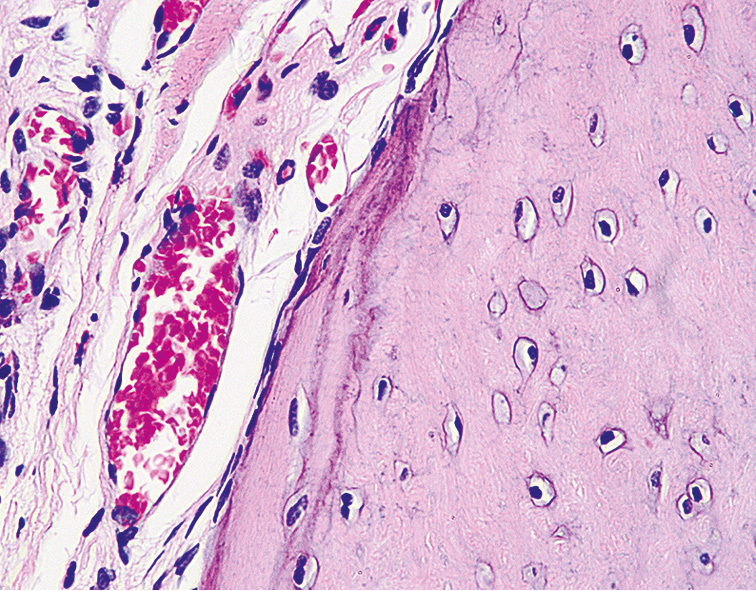

Проведенные гистологические исследования СОП животных опытной группы через 7 мес после ДМГ поражения позволили выявить глубокие деструктивно-дегенеративные изменения всех ее компонентов. Так, среди фрагментов гиалиново-волокнистой хрящевой ткани отмечались скопления фиброретикулярных клеток костного мозга с примесью жировых включений, а также опухолевые клетки (рис. 7). В этот же срок эксперимента для тканей СОП животных были характерны элементы костного мозга в прослойках хрящевой ткани, что приводило к утолщению стромальной соединительной ткани и фиброзу (рис. 8).

Рис. 7. Слизистая оболочка пасти животного (опытная группа) через 7 мес от начала эксперимента. Окраска гематоксилином и эозином, ×280.

Fig. 7. The mucous membrane of the animal’s mouth (experimental group). after 7 months from the beginning of the experiment. Staining with hematoxylin and eosin, ×280.